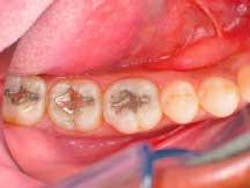

After applying the dentin material, the clinician placed a .5 mm layer of medium value enamel material, followed by the final layer of clear transenamel material, using the same buildup and curing technique as specified for the dentin layers. A final cure of each restoration was performed from the occlusal aspect for 30 to 40 seconds per tooth (Figure 4).